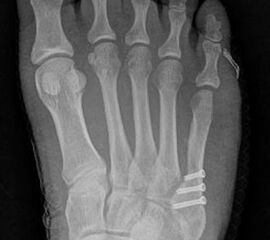

Abb. 3a, b: Präoperatives (a) und postoperatives (b) Röntgenbild bei Korrektur einer Typ I Deformität durch eine Exostosenabtragung.

Abb. 4a, b: OP Bilder bei lateraler Exostosenabtragung. Nach Hautschnitt ist die teilweise rupturierte laterale Gelenkkapsel erkennbar (a) mit Bursagewebe. Nach Resektion der Bursa und Abtragung der Exostose zeigt sich eine spongiöse Fläche (b) vor dem Wundverschluss.